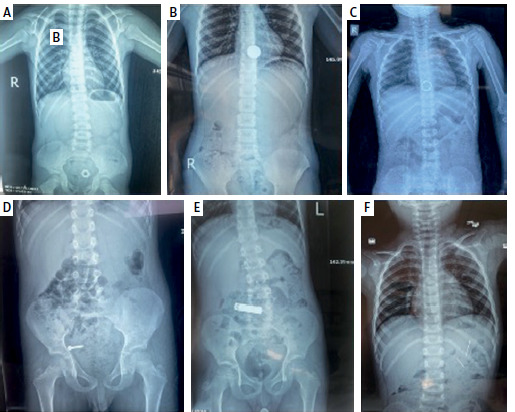

Results: Fifty-four patients visited or were admitted to the Rapareen Hospital Emergency Department with a history of ingestion of foreign bodies, with a median age of 4 years (mean age: 4.14 ±2.15 years) and a nearly equal male-to-female ratio (1.16 : 1). Most of the foreign bodies were radiopaque, and the majority were located in the oesophagus at the time of initial presentation. Disc batteries (27.8%) were the commonest foreign body, followed by coins (20.4%), of which 66.7% were retrieved endoscopically, while 4 patients needed surgical intervention. Cross-tabulation reveals a significant association between the site of materials and the early presentation, type of object, and outcome. Also, a significant association was established between the type of foreign body and gender, age, time of presentation, and outcome.

Conclusions: The button battery was the most common foreign body ingested among the children, and the majority were located in the oesophagus and extracted by endoscopy.